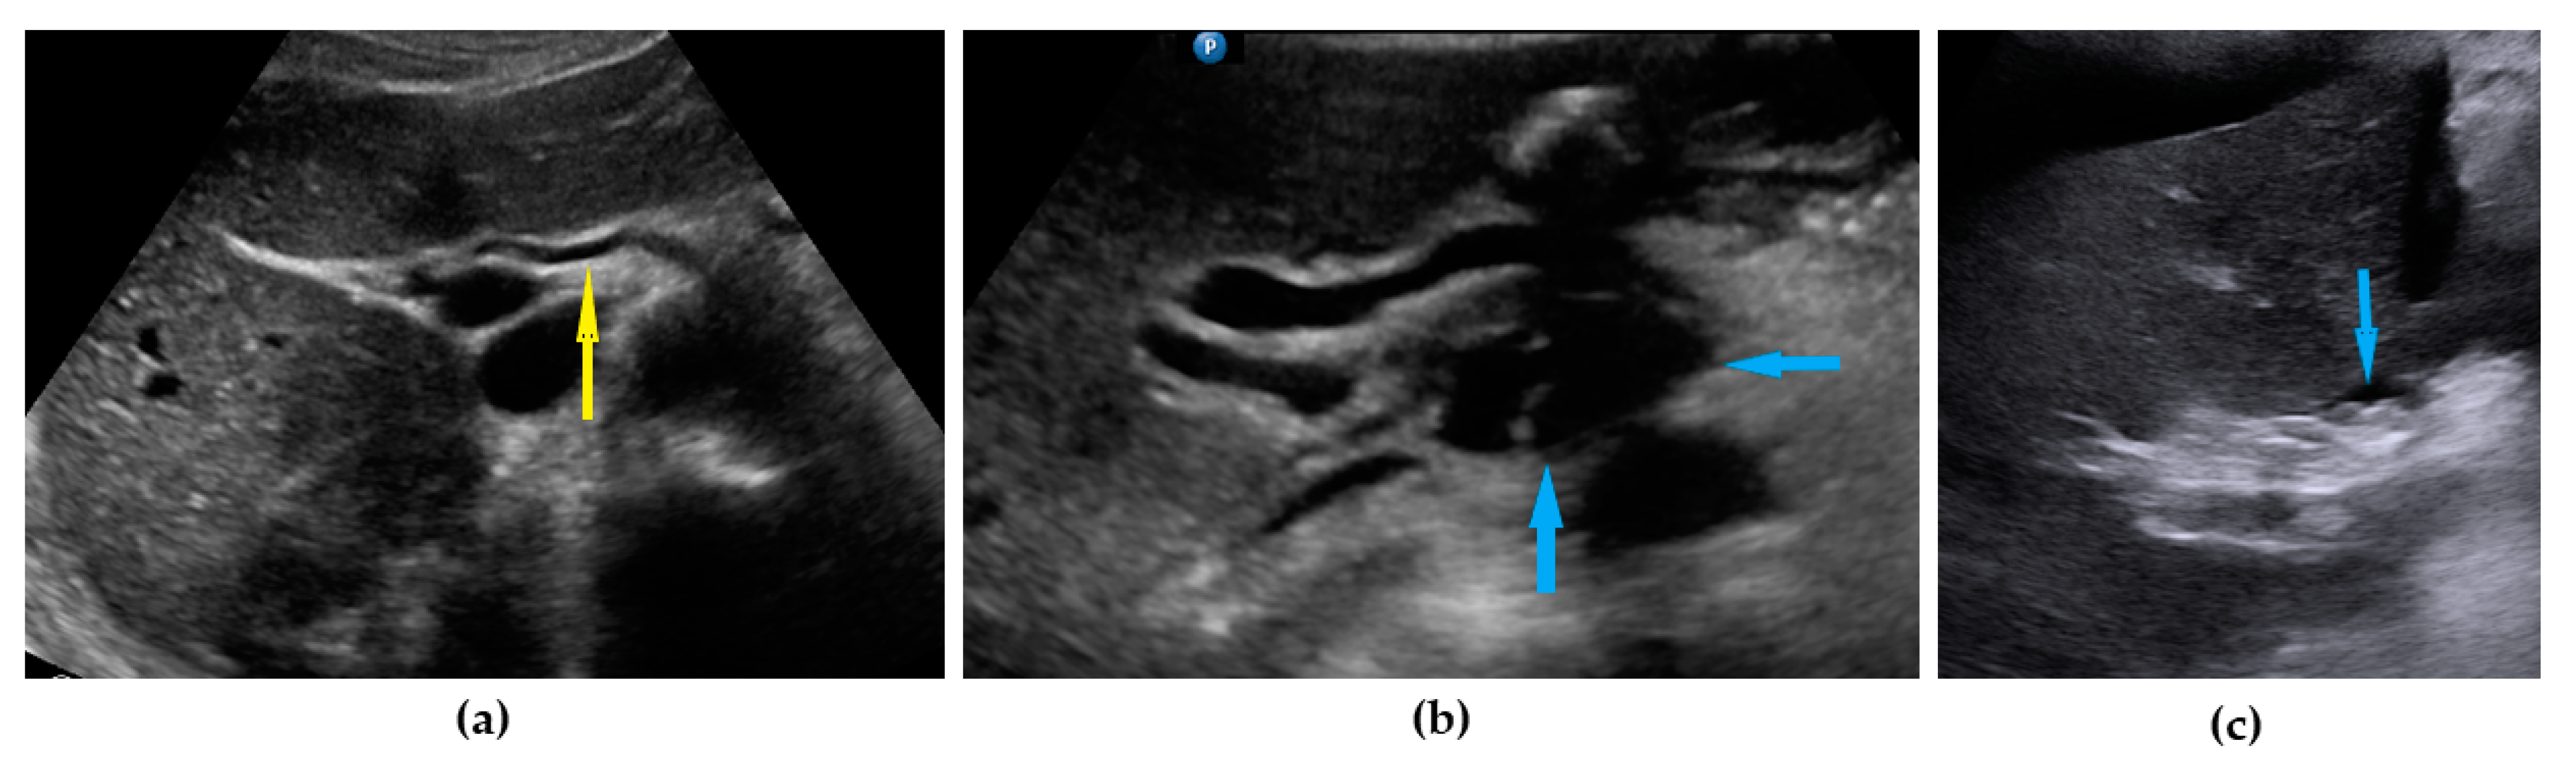

| Frozen pelvis | Massive pelvic involvement: hypoechogenic tissue in the peritoneum in the pouch of Douglas, forming cohesion between ovarian masses, bowel, uterus, and posterior pelvic wall. It manifests in the dynamic ultrasound examination: absence of sliding sign between the rectum and uterus/ovaries and between the uterus, urinary bladder, and pelvic walls. | Figure 12 | Video S12 |

| Rectum-sigmoid | Suspected involvement of the rectosigmoid wall manifests as the presence of metastases over the wall of the rectum or sigmoid. | Figure 13 | Video S13 |